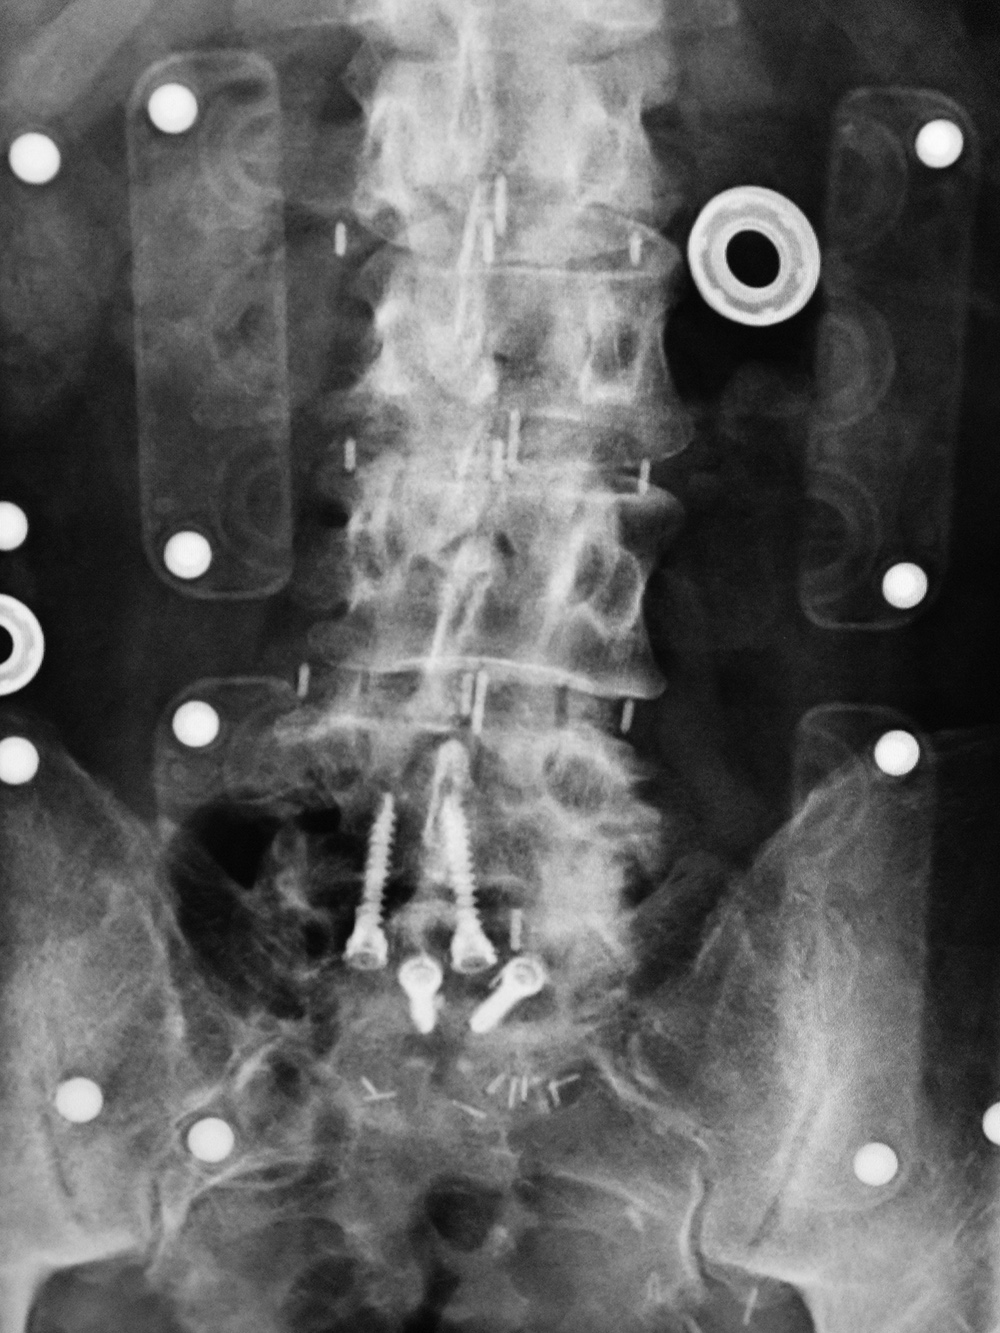

Lumbar spine bony disk strut, pedicle screws, and pedicle rods (AP view) |